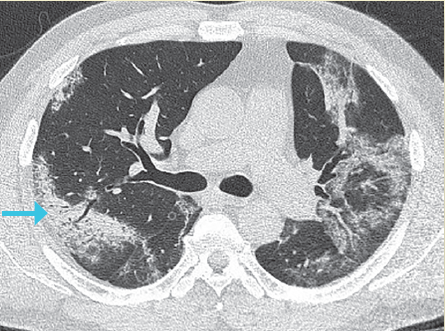

Estadio 3: De 9 a 13 días. Se observó un patrón de consolidación en el 91% de los pacientes. El área involucrada crece lentamente (figura 4).